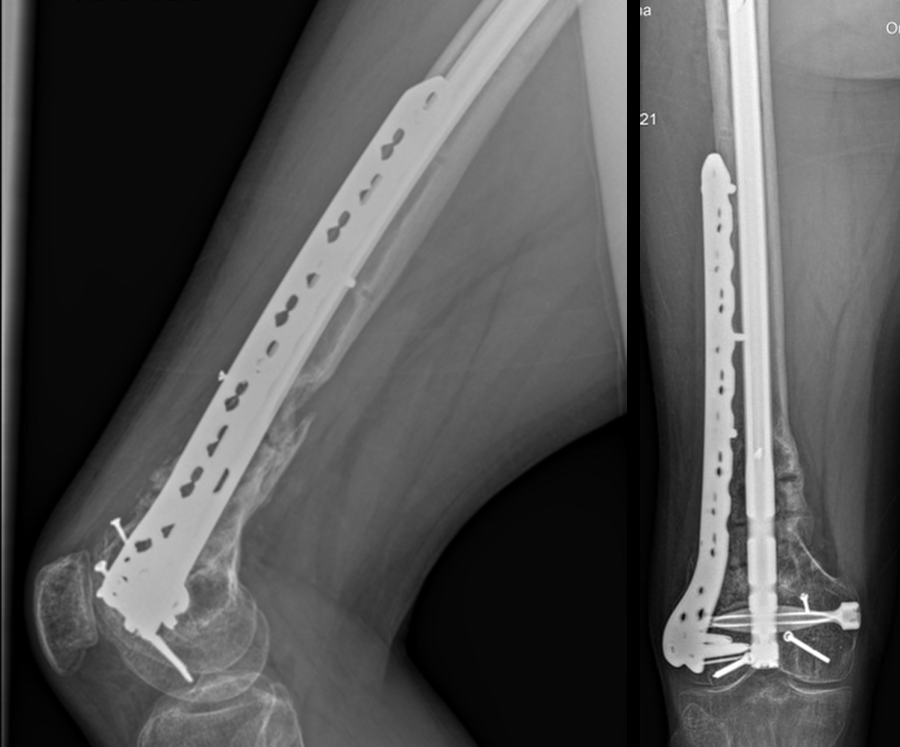

Following the advent of Covid-19 in early 2020, the patient was lost to follow-up for almost one year and was eventually seen again in December 2020 (Fig 8). At this follow-up, a CT scan was planned for the right distal femur and a graft cage ordered. Surgery was scheduled for early 2021.

At the 3-week follow-up (post-graft cage, Fig 12), the patient’s wounds were healthy. He had a range of motion (ROM) of 0–80 in his right knee. He was allowed weight bearing as tolerated (WBAT) with crutches.

At the 3-month follow-up (Fig 13), the patient had a ROM of 0–120 in his right knee. His quadricep muscles had significantly recovered and he was able to WBAT with support from a cane.

At the 6-month follow-up (Fig 14), the patient was able to WBAT on the right lower extremity. He had some ankle pain and a ROM of 0–125 in his right knee. The patient was able to walk without any assistance device.

At the 9-month follow-up (Fig 15), the patient reported nominal knee pain, but more pain in his ankles. The patient had returned to work. He was not undertaking any heavy lifting but was driving the truck and supervising the team. Overall, the patient was happy with the current outcome of surgery.